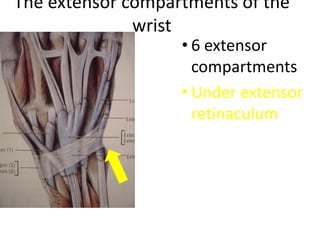

- It describes flexor tendon zones, extensor compartments, and pulley system anatomy.